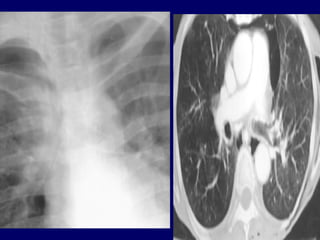

Bronchiectasis is defined as localized bronchial

bronchial wall thickening

lack of normal tapering with visibility of airways

in the peripheral lung

Tram Tracks

Bronchial dilation with lack of tapering .